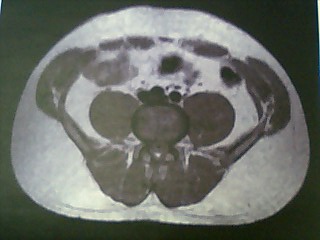

まずは開始前の2006年4月。

このときのMyBodyは以下の通り。

身長 172cm / 体重 80.7kg

体脂肪率 25.3% / 筋肉率 31.4% / BMI 27.2

いや~、見ていると気持ちが悪くなってきます